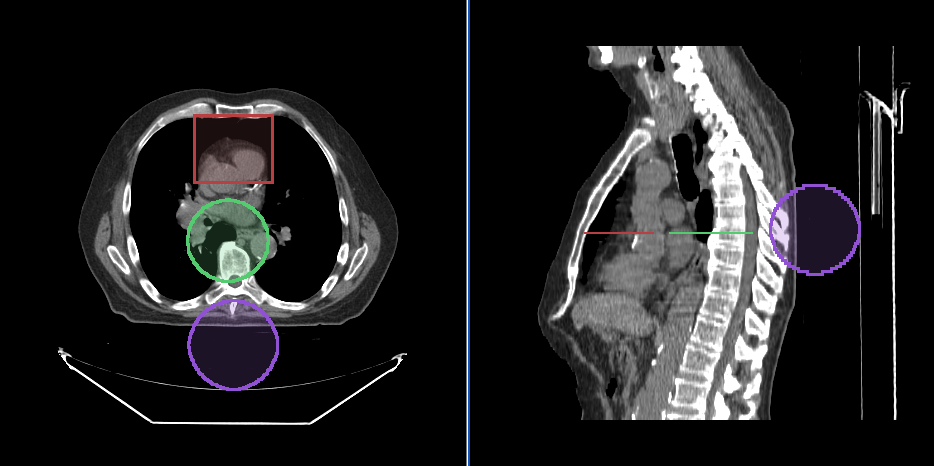

Annotation sharing in Frame of Reference

Since, annotations are stored in the patient physical space, if there are two viewports that are displaying the same frame of reference, they will share the same annotations.

Segmentation Tools

Cornerstone3D also provides segmentation tools. This includes 3D SegmentationDisplay

and 3D segmentation editing tools such as brush, rectangle and circle scissors, and

3d sphere tools.

We will discuss in length the different types of segmentation tools and how they

are used in Cornerstone3DTools in Segmentation section.